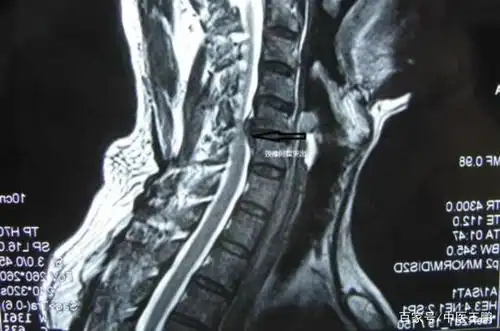

颈椎压迫神经是怎么回事?